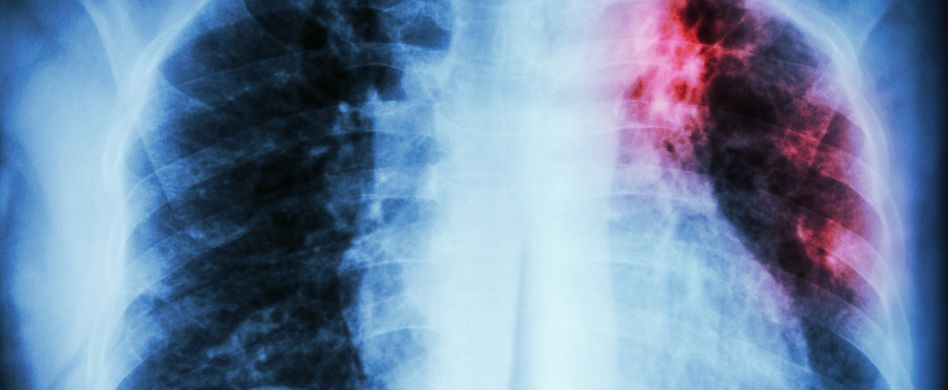

Verdacht auf Lungenfellentzündung – zu welchem Arzt muss ich?

Haben Sie den Verdacht, an einer Lungenfellentzündung erkrankt zu sein, sollten Sie unbedingt einen Arzt aufsuchen. Der Lungenfacharzt (Pneumologe) wird verschiedene Untersuchungen veranlassen, um die Ursache Ihrer Beschwerden herauszufinden, darunter Ultraschall-, Röntgen- und Laboruntersuchungen. Die Symptome können auch bei einer Reihe anderer Lungenkrankheiten auftreten. Daher ist eine gründliche Untersuchung wichtig.